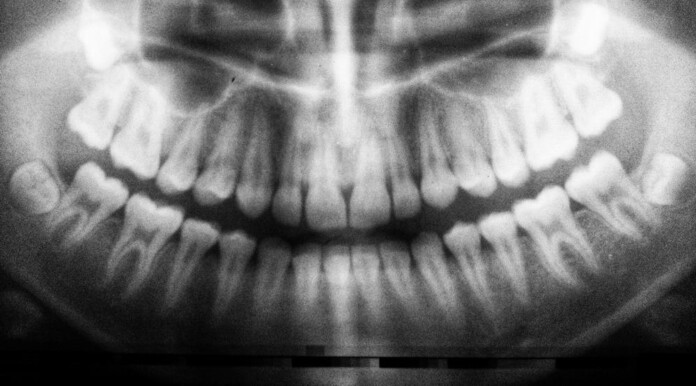

Wisdom Teeth Contain Unique Stem Cell That Can Form Cartilage, Neurons, and Heart Tissue

If they don’t grow in right, most people will treat their wisdom teeth as bio-baggage, useful only for preventing money from burning a hole in one’s pocket due to the surgical costs of removing them.

But an astounding new discovery has found that this third set of molars contain a unique form of human stem cell that can be harvested and used to regrow bone, heart tissue, and even neurons.

For starters, wisdom teeth contain a soft center of tissue called dental pulp that keeps the tooth alive. This pulp contains immature cells which a team of scientists at the University of the Basque Country in Spain have transformed into several different kinds of cells.

Dr. Gaskon Ibarretxe, an associate professor in the Cell Biology and Histology Department at the university, led a recent study that turned pulp cells into electrically excitable pseudo-neurons that demonstrated “essentially electrical activity” in concert with proper neurons.

According to Earth.com, pulp-derived stem cells have some interesting and unique properties, including the capacity to build mineralized tissue faster than bone marrow-derived stem cells. Scientists have used dental‑pulp secretions to improve heart ejection fractions in mice with heart failure, and in vitro, these cells seem to lay down layers of collagen and calcium in neat, orderly sheets, making them potentially attractive for joint cartilage repair.

By contrast, almost all humans are born with wisdom teeth, and they’re often removed in the teenage years when little DNA damage has taken place inside the dental pulp; making them exceptionally malleable and safer.

Earth.com claims 10 million wisdom teeth are removed every year, but the process of sending them to a biobank could be very simple. A kit—offered by a company like Stemodontics—could be bought and shipped to a dentist’s office ahead of the procedure. The tooth is put in a vial, placed on dry ice, and rushed to a lab where the pulp would be extracted and preserved as a potentially life-changing form of cellular insurance.